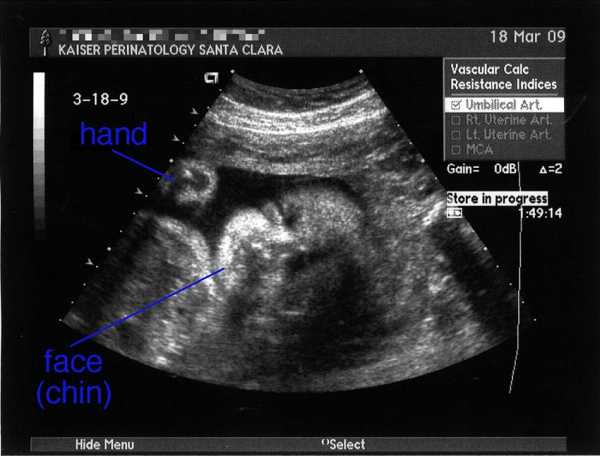

УЗИ на 31 неделе беременности

На 31 неделе беременности с помощью УЗИ можно будет определить положение ребенка, его предположительный рост и вес во время родов. Именно сейчас можно понять, будут ли роды проходить естественным путем или с помощью кесарева сечения. Однако, решение может измениться по ходу беременности: никто не может дать 100%-ных гарантий правильности развития плода.

Очень увлекательно наблюдать за действиями младенца в утробе: он уже не маленькое пятно, похожее на персик, а человек, который что-то умеет и знает. Можно увидеть, как он сосет пальчик, играет с пуповиной. Если малыш сосет палец на правой руке, то, скорее всего, родится правша, если левой – то левша.

На 31 неделе беременности можно с вероятностью 99% говорить о половой принадлежности ребенка, если, конечно, родители не хотят сделать себе сюрприз. На самом деле совсем не важно, кто это будет, девочка или мальчик, главное, чтобы малыш родился здоровым.

Важность УЗИ неоспорима. Иногда будущие матери отказываются от исследования, аргументируя это тем, что раньше женщины рожали и без него. Но сейчас наука идет вперед, с помощью этих недолгих манипуляций можно предсказать болезни или возможные нарушения в организме малыша. Отказываясь от врачебной помощи, будущая мать рискует здоровьем и жизнью своего ребенка.

Фото УЗИ на 31 неделе беременности

к содержанию ↑УЗИ на 31 неделе беременности

На 31-34 неделе беременные женщины проходят третье ультразвуковое сканирование. При наличии определенных показаний специалисты назначают дополнительные УЗИ. В процессе исследования на 31 неделе: определяется предлежание; выясняются значения фетометрических показателей; оценивается анатомия плода; определяется расположение плаценты, ее толщина, выявляется обвитие вокруг шеи плода; дается оценка двигательной активности плода.

Третье УЗИ — это итоговый контроль за состоянием плода, его положением, оценка функциональности плаценты и выбор метода родоразрешения. Это плановое ультразвуковое исследование чаще всего показывает следующие ненормальные состояния:

- плод в поперечном положении;

- плод в косом положении;

- предлежание плаценты;

- многоводие;

- заболевания, которые ранее не были выявлены.

В ходе УЗИ также оценивается анатомия плода. Здесь указываются внутренние органы и отмечается, присуща ли им норма, нету ли каких-то патологических изменений. Также в документе даются характеристики плаценты. Они отражают ее способность снабжать плод всеми необходимыми веществами.